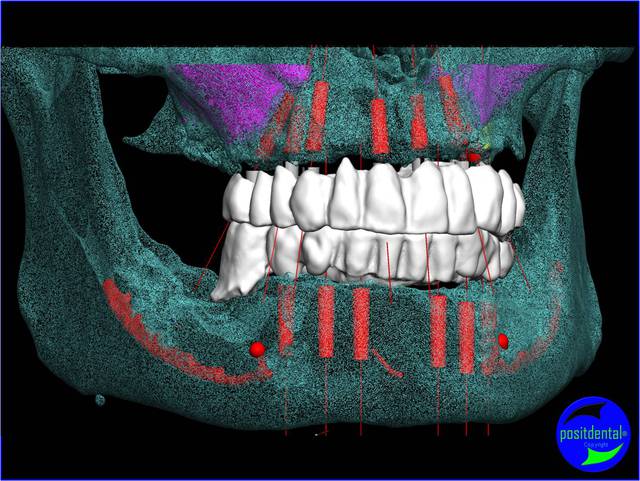

photo 1 lundi

Extractions, pose des implants, pose des multis-units, pose des bridges provisoire en une chirurgie. Cas 1 et 2 implants MIS, 3 BREDENT. Photo du provisoire 1 et 3 prise dans la suite de l'intervention chirurgicale, 2 prise à 48h.

Pano de contrôle à 40 J post op